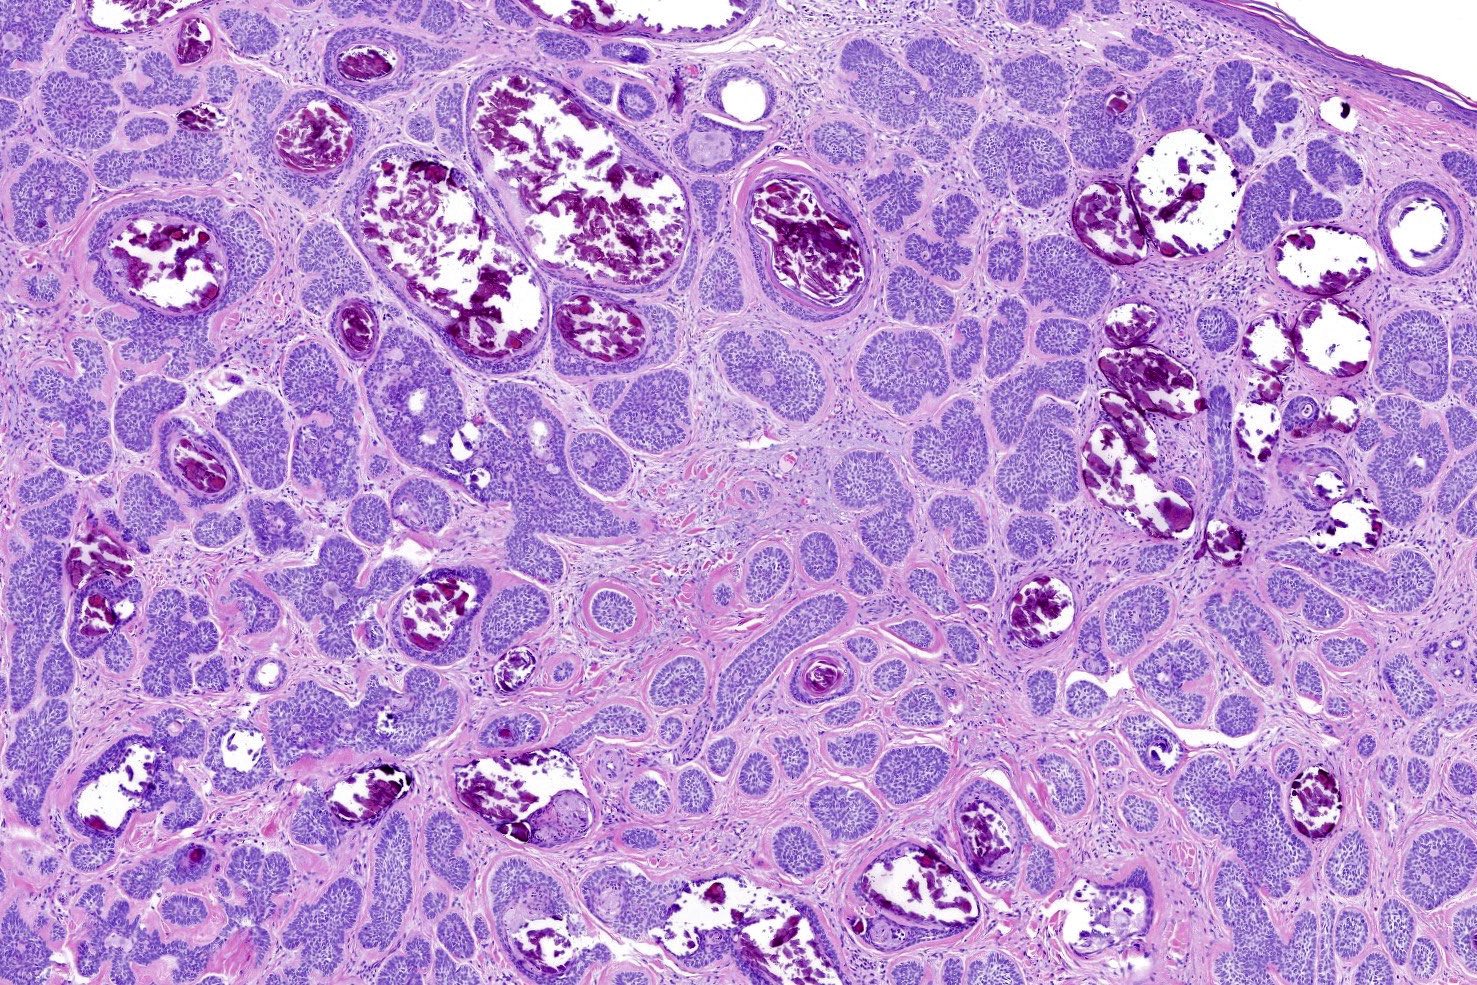

- Nodular and nodulocystic BCC

- Relatively circumscribed mass

- Epidermal or follicular attachment variably present

- Large basaloid lobules with peripheral nuclear palisade

- Lobules may be solid or show central cyst formation due to excessive mucin production

- Fibromyxoid stroma

- Cleft formation between tumor lobules and stroma

- Pleomorphism is generally mild

- Variable mitotic activity and apoptosis

- Micronodular BCC

- Small basaloid nests

- Peripheral palisading less prominent

- Retraction artifact usually absent

- Can diffusely infiltrate the dermis and extend into the subcutis